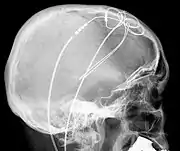

Mrs Geraets-Smits claimed the refusal of reimbursement for treatment for Parkinson’s disease in Kassel, which she believed was better than that available in the Netherlands by focusing on individual symptoms, was contrary to TFEU article 56. Mr Peerbooms received neurostimulation treatment in Innsbruck, which likewise would not have been covered in the Netherlands. Experts testified in both cases that it was unjustified or experimental. Dutch social insurance covered medical costs of low income people, but only if it was approved. Funding came from individual premiums, from the state, and some from other private insurance funds. Geraets-Smits and Peerbooms had paid up front in Germany and Austria. Dutch law said authorisation had required that (1) treatment had to be regarded as ‘normal in the professional circles concerned’, and (2) ‘necessary’ so that adequate care could not be provided without undue delay by a care provider in the home state. The prior authorisation requirement was challenged as being contrary to TFEU article 56. Governments submitted that hospital services were not an economic activity if it was provided free of charge under a sickness insurance scheme.